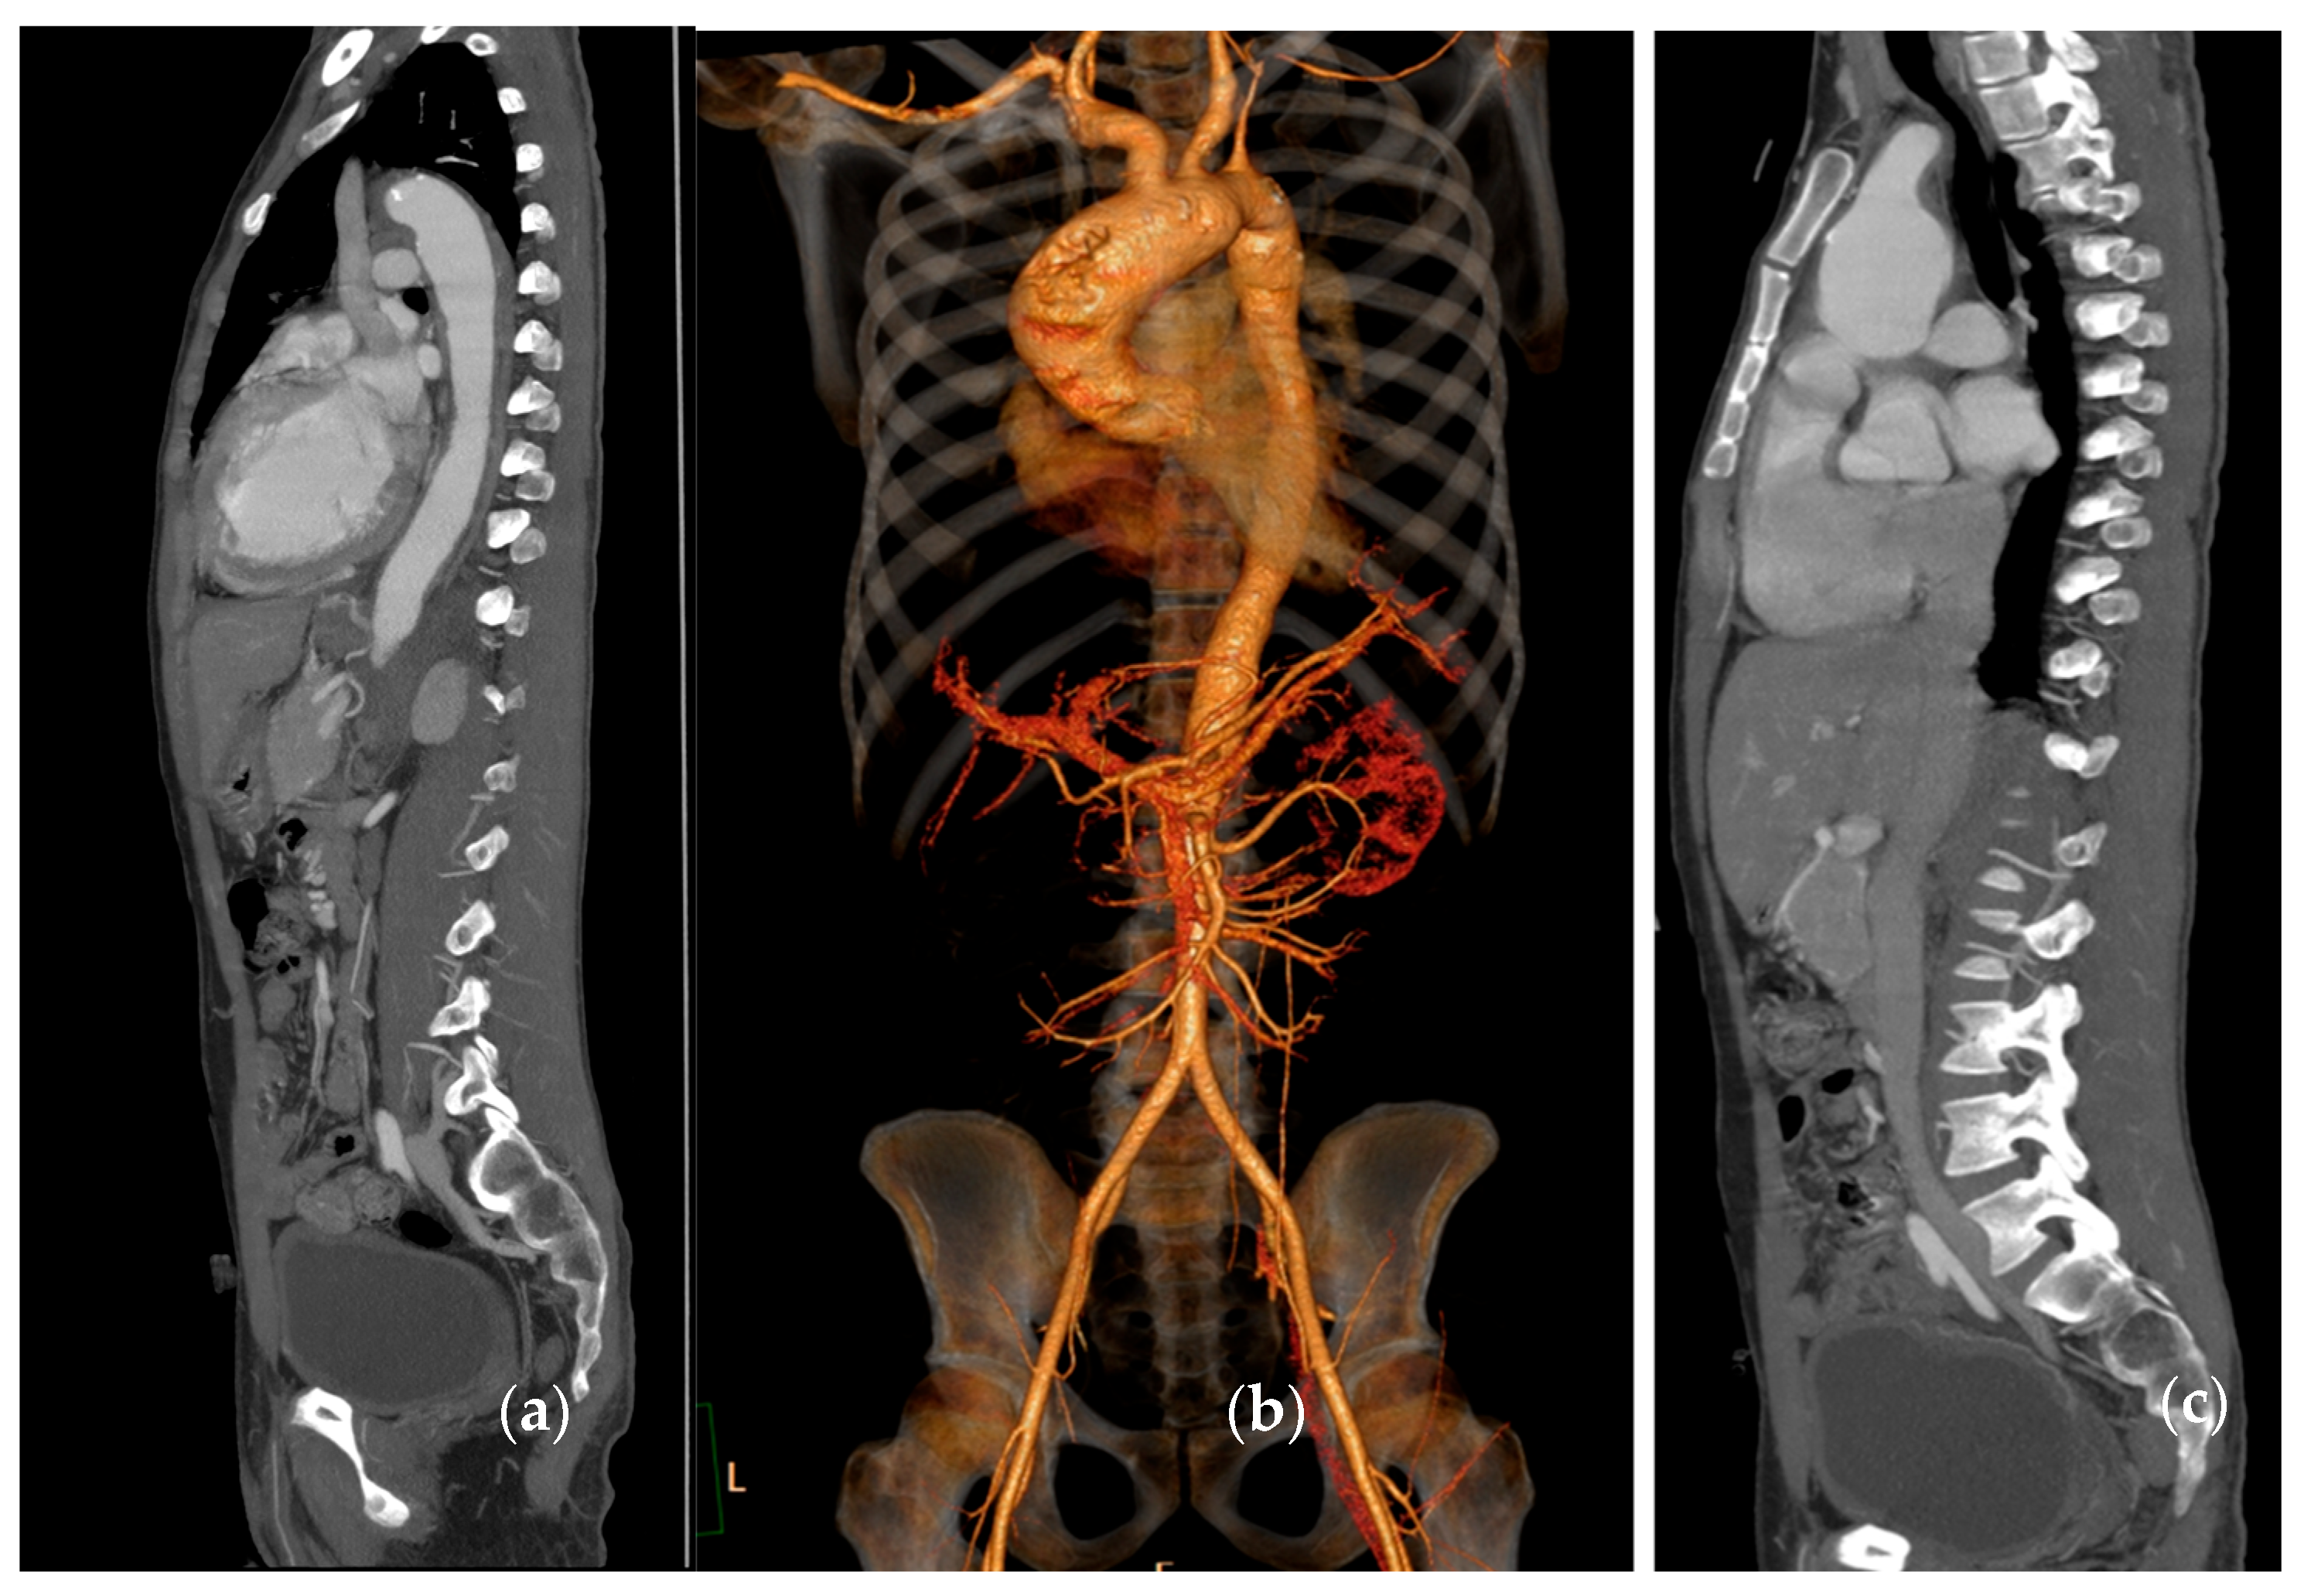

| CT/CTA | High; wide anatomic coverage. | High for vascular structural characterisation; poor for inflammatory changes. | Better suited for evaluating chronic vascular damage rather than active inflammation. | Widely available; rapid acquisition time; enables anatomic mapping. | Ionising radiation; use of iodinated contrast; limited ability to detect active inflammation. |